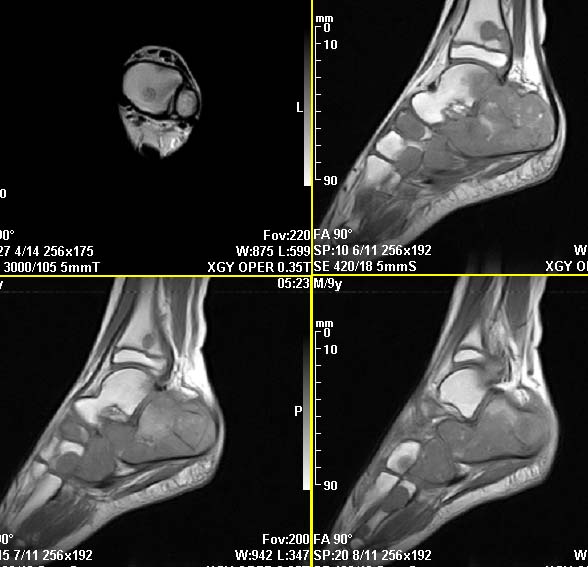

m,9y,左足肿痛半年,无皮肤发红,诱因为外伤后起因。无发烧,无其他疾病。临床考虑多发血管瘤。mri增强后有强化,请分析。是骨髓瘤吗?

左足多发囊状膨胀性骨质破坏,边较清,关节间隙及软组织未见明显异常。结合临床。可排除炎症性病变。病变中心为骨髓腔。有强化。中心坏死。嗜酸性肉芽肿可能大。

多发内生性软骨瘤

结合临床考虑血管瘤侵犯左足骨质。

今天从天津肿瘤医院传来消息:病理结果是非骨化性纤维瘤。